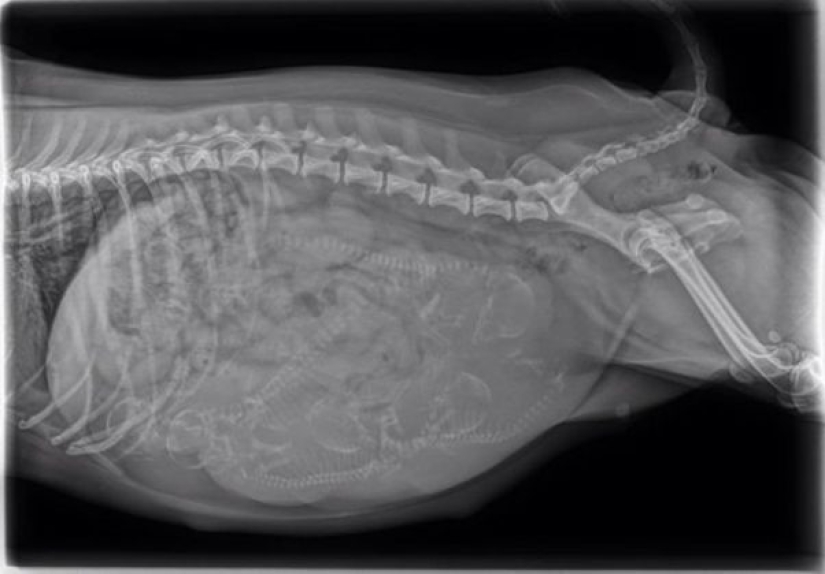

9. This is what a translucent cat looks like: